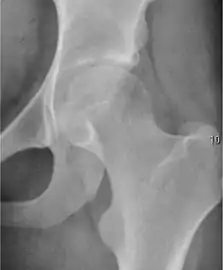

- Slipped capital femoral epiphyses (SCFE)

Slipped capital femoral epiphyses (SCFE) usually affect 11- to 14-year-old adolescents (Figure 4). Radiographs may show widening and irregularity of the physis and posterior inferior displacement of the capital femoral epiphysis. On the AP view Klein’s line, tangent to the lateral aspect of the femoral neck, does not intersect the femoral head indicating that it is displaced. SCFE may compromise the blood supply to the femoral head and cause avascular necrosis, mainly when there is instability between the fragments.[1]

Figure 4: (a) X-ray of a 10-year-old child with left hip pain. It was considered normal at emergency despite the widening of the left physis (arrow). Two weeks later epiphysiolysis was evident (b). Despite appropriate surgical reduction (c) osteonecrosis developed and femoral head collapsed 1 month later (d).[1]